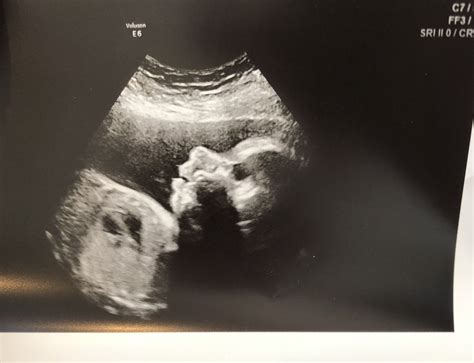

28 Weeks Sonography is a routine ultrasound scan conducted during the third trimester of pregnancy. This scan is often referred to as the "anomaly scan" or "mid-pregnancy scan" and is usually performed between 26 and 28 weeks of gestation. The primary goal of this ultrasound is to assess the baby's growth, development, and overall health. It also helps in identifying any potential complications that may require further monitoring or intervention.

During a 28 Weeks Sonography scan, the expectant mother will lie on an examination table with her abdomen exposed. A gel is applied to the abdomen to enhance the transmission of ultrasound waves. A transducer, a handheld device, is then moved over the abdomen to capture images of the baby. The procedure is painless and non-invasive, typically lasting between 20 to 30 minutes.

These measurements help in estimating the baby's weight and assessing overall growth. The technician will also check for any structural abnormalities in the baby's organs, such as the heart, brain, kidneys, and spine.

Additionally, the 28 Weeks Sonography scan can provide a clearer view of the baby's gender, although this is not the primary purpose of the scan.